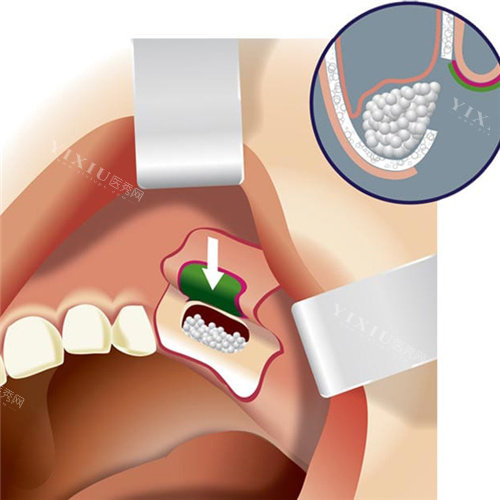

GBR植骨则采用不同的原理,利用屏障膜将软组织隔离,引导成骨细胞在植骨区域生长,同时填充骨粉或自体骨颗粒。这种技术不需要额外取骨,操作过程相对简单,但需要注意屏障膜的固定和空间维持,这对手术结果有重要影响。

GBR植骨的适应症范围相对较广,适用于较小范围的骨缺损,如种植体周围骨缺损、拔牙后即刻植骨等情况。这种技术特别适合水平向骨增量,在临床应用中较为普遍。

GBR植骨在操作规范的情况下,骨吸收情况相对可控,短期结果通常较好。但对于大范围骨缺损,可能需要结合使用钛网、帐篷钉等辅助技术来维持空间,以确保治疗结果。

GBR植骨在短期骨增量方面结果较好,但在处理大范围缺损时,可能会出现骨粉塌陷、膜暴露等问题。这些问题需要通过合理选择材料和辅助技术来预防和解决。